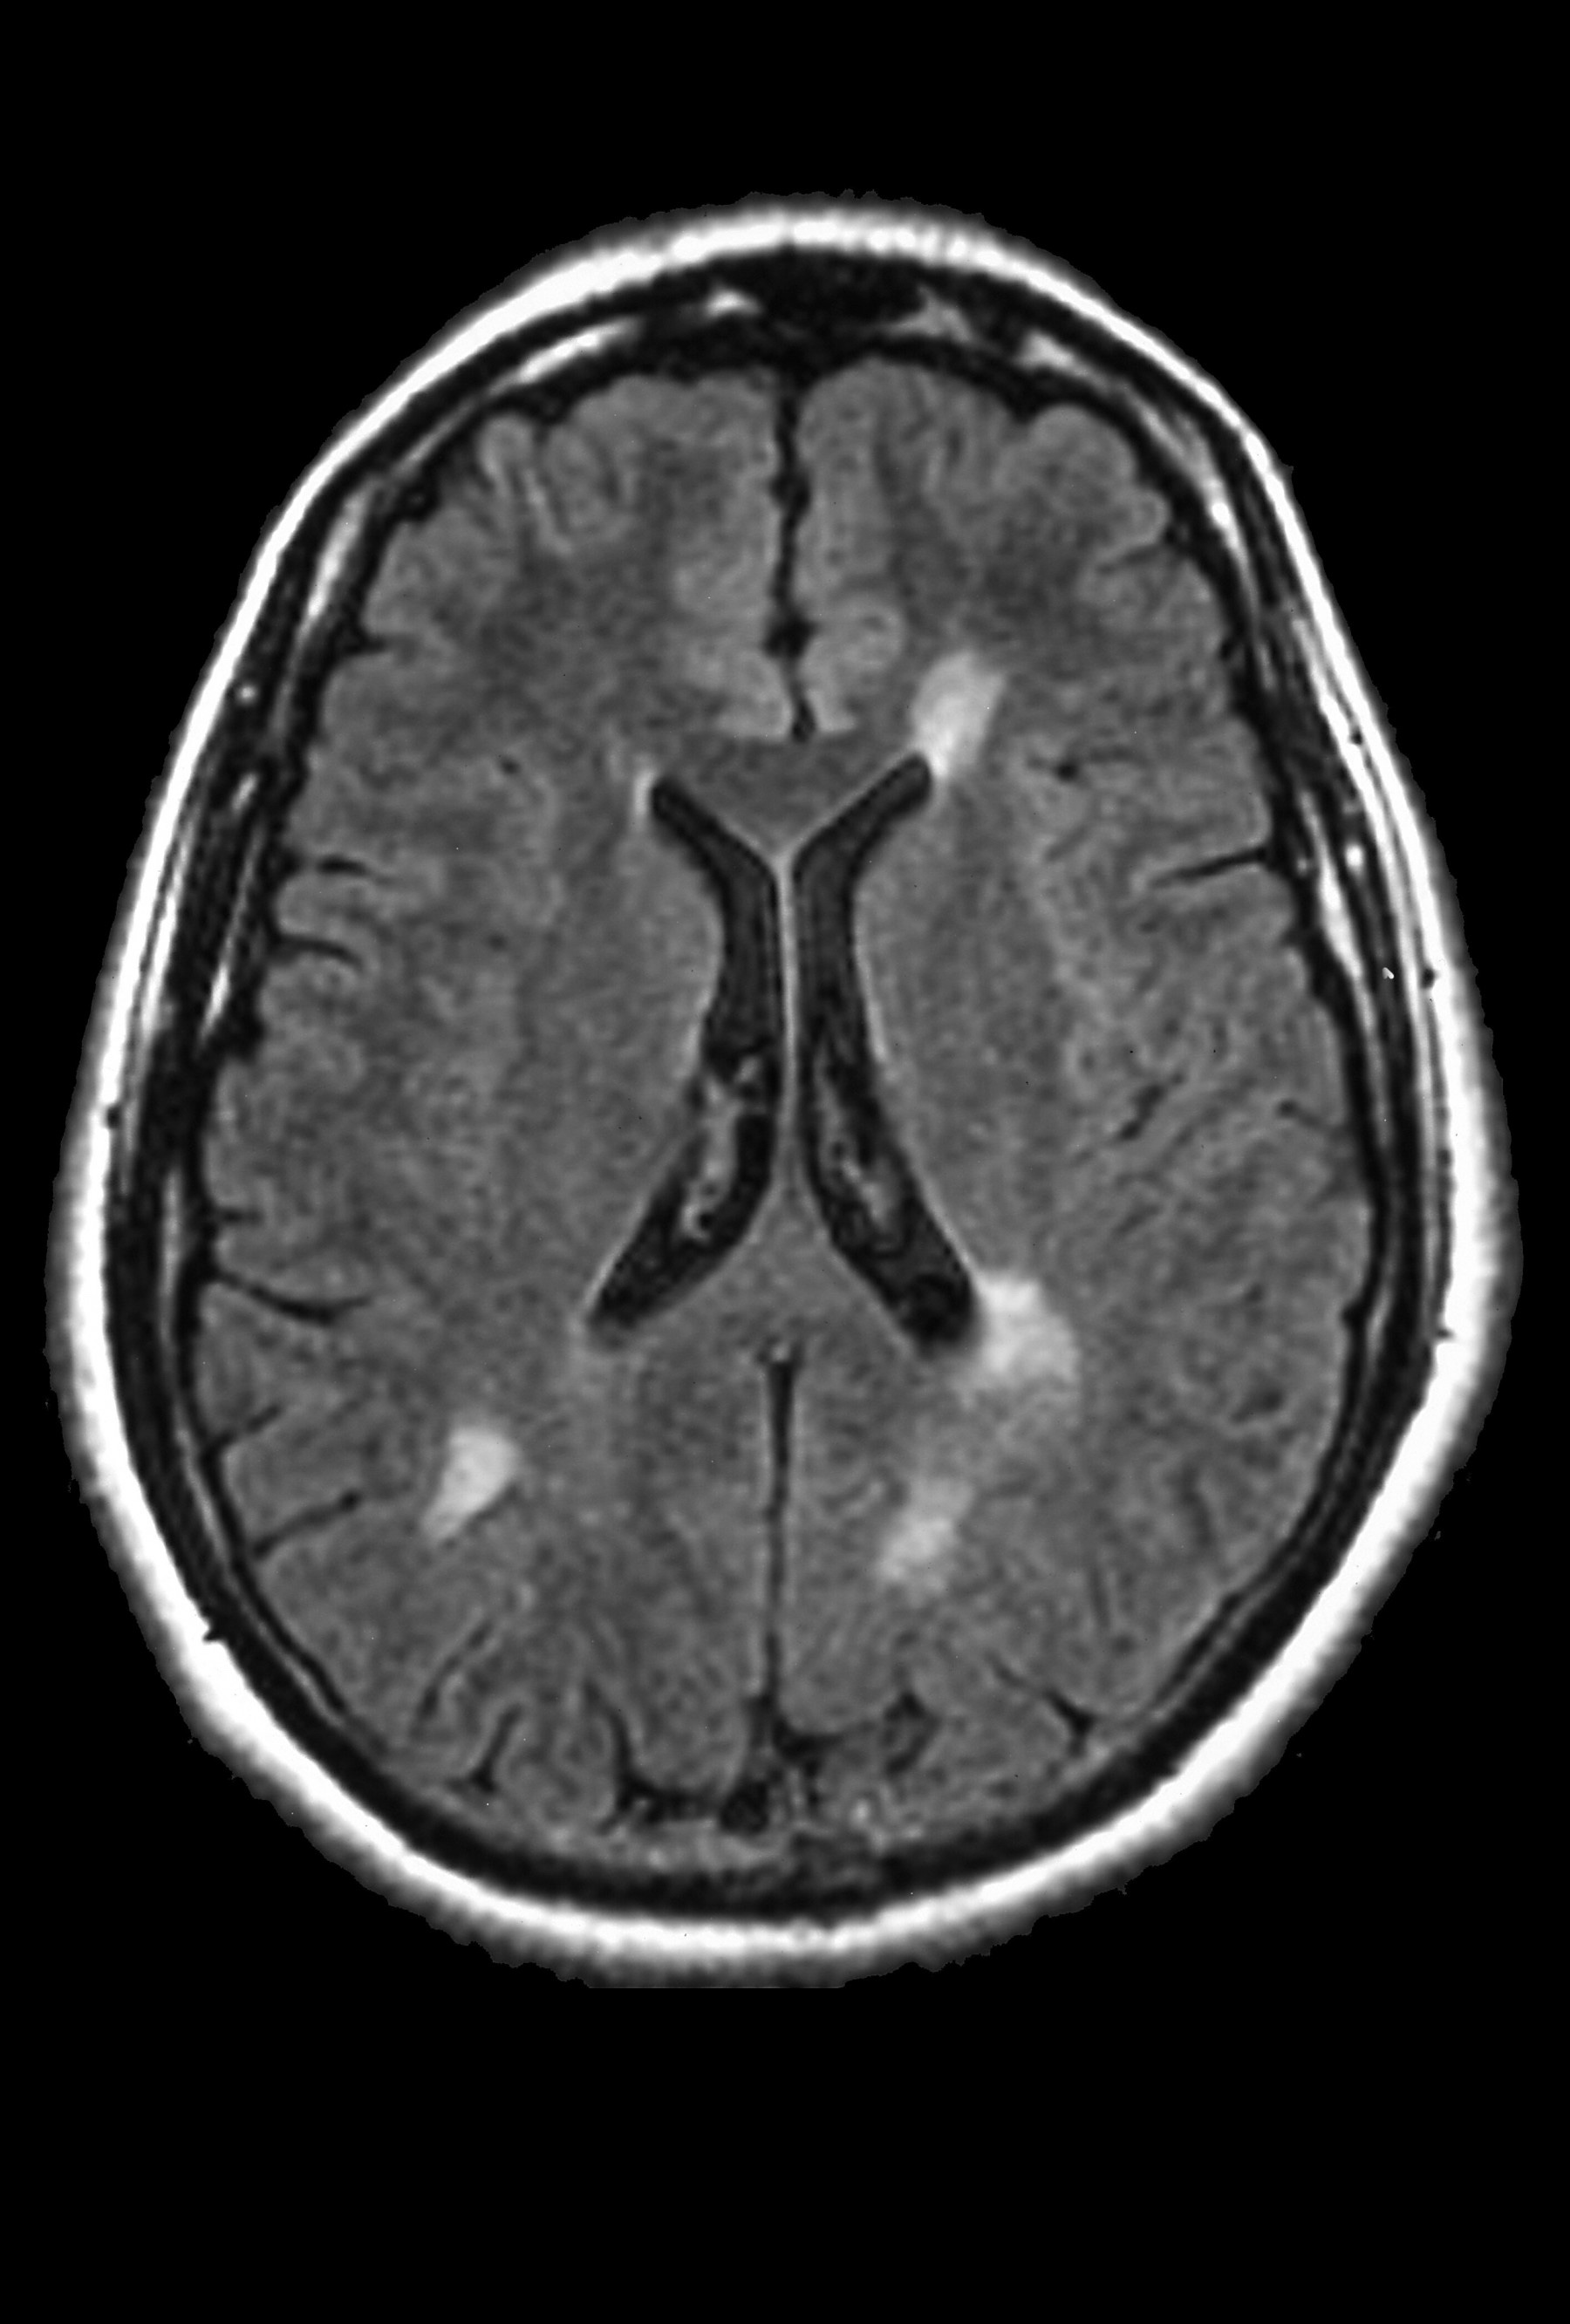

Multiple Sclerosis Radiology Cases

from radiologycases.my